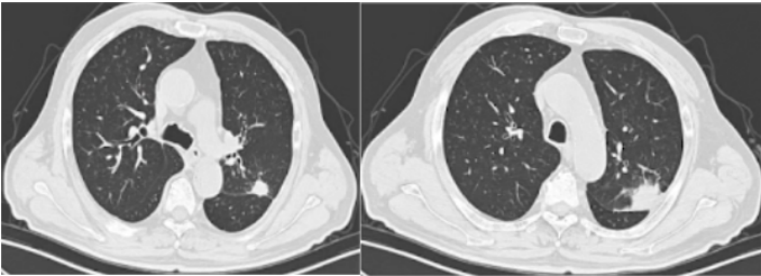

Lemierre综合征(LS)是以法国医生Andre Lemierre的名字命名,他在1936年报告了20例由口咽感染引起的厌氧败血症。(1)流行病学:在抗生素广泛应用的年代,LS的发病率急剧下降。自70年代后期口腔感染中经验性抗生素的使用减少,报告的病例数量稳步上升,被称为“被遗忘又重现的疾病”,发病率为每年1/10000000,通常为青少年和年轻人,即使使用适当的抗生素和治疗,报道死亡率也在5%~18%之间。(2)致病菌:导致LS的致病菌通常为坏死梭杆菌(>70%),它是严格的专性厌氧革兰氏阴性杆菌。(3)病理生理:首先由于细菌、病毒致咽部黏膜损伤,在此基础上出现坏死梭杆菌的二重感染:①感染至咽外侧间隙和颈部软组织,引起外源性压迫,出现炎症、水肿;②内源性闭塞,出现血管内凝血。在上述基础上发生颈内静脉脓毒性血栓形成;感染性栓子从任何一条静脉播散,都可能导致肺、胸膜、关节、骨骼、肌肉、肝、脾、肾等多处器官受累。(4)临床特征:①口咽感染;②颈内静脉血栓性静脉炎感染延伸至颈部旁间隙;③脓毒性栓子播散引起菌血症、脓毒性休克。(5)诊断:①血培养:培养时间需要6~8天,阳性率低;②分子生物学方法:快速且准确,有助于早期诊断;③BALF、m-ROSE、NGS等。LS的Sinave诊断标准:①口咽部的原发感染;②脓毒败血症;③颈内静脉感染性栓塞;④远处脏器转移性化脓灶。(6)治疗:①抗菌药物治疗:碳青霉烯类、β-内酰胺/β-内酰胺酶抑制剂联合甲硝唑是治疗LS最有效的药物。②抗凝治疗。③外科治疗。(1)定义:齿垢密螺旋体是一种螺旋形的革兰氏阴性厌氧菌,属解糖密螺旋体,与口腔以及牙周感染性疾病密切相关。(2)流行病学:关于齿垢密螺旋体,近4年来仅有寥寥数篇报道,极为罕见。(3)易患人群:长期卧床、生活无法自理导致口腔卫生较差、牙周状况不理想、免疫功能低下的老年人。(4)临床症状:多为非特异性症状,可有吸入性肺炎的一系列临床表现,如咳嗽、咳痰、甚至咯血,也可有畏寒、发热等。(6)治疗:目前仍按照密螺旋体属中常见人致病螺旋体进行治疗,首选为青霉素,其他如半合成青霉素、四环素类等药物亦有较好效果。患者男性,72岁。主诉:间断咳痰、咯血1月半余,发现肺结节1月余。患者2023年2月中旬无明显诱因出现间断咳痰,咳白黄痰,痰中带血,每天5~6次,无发热,无胸痛等不适,后出现咯鲜血,咯绿豆大小血块,4~5次/天,就诊于当地医院,胸部CT提示左肺上叶占位,予莫西沙星抗感染治疗约1周后症状好转,后就诊于我院。入科后,予患者支气管镜下肺泡灌洗并将BALF送检mNGS,结果回报检出齿垢密螺旋体(序列数36条)。予哌拉西林他唑巴坦4.5 g q8h+米诺环素100 mg q12h抗感染,调整治疗方案为美罗培南1 g q8h,后期仅采用替加环素50 mg q12h治疗。抗感染治疗后,患者左肺上叶结节明显缩小。非典型病原体是一种细胞内或细胞旁的细菌病原体,无法通过革兰氏染色和传统培养基进行识别,对β-内酰胺具有内在耐药性。2022年Microorganisms杂志发表的综述显示,在CAP病因中,非典型病原体占15%,这其中,肺炎支原体位居首位,其次是肺炎衣原体,然后是嗜肺军团菌以及鹦鹉热衣原体等。1976年夏天宾夕法尼亚州费城Bellevue-Stratford酒店举行的为期3天的美国退伍军人协会年度大会上,嗜肺军团菌感染首次被发现。(1)流行病学:既往军团菌肺炎的病死率可达10%~15%,院内感染死亡率可达25%~50%。随着喹诺酮类药物的临床应用,该病病死率有所下降。该病发病具有季节性,全年均可发生,以6~10月发病最多。(2)致病菌:军团菌肺炎的致病菌通常为嗜肺军团菌血清型1,约占90%,是一种需氧革兰氏阴性杆菌,细胞内寄生菌,双相生存周期。(3)传播途径:军团菌广泛存在于自然界中,尤其是温暖潮湿的环境,如人工冷水、天然水源、潮湿土壤等。军团菌感染多通过吸入受污染的人造水源(如淋浴、管道、空调系统等)产生的含军团菌气溶胶。(4)易患人群:>50岁、吸烟、免疫抑制(尤其是细胞免疫抑制)、合并慢性心肺疾病等。(5)影像学表现:肺部变化通常为单侧,主要局限于下叶,但也可能出现在两侧,包括肺部的上下部分;肺部的炎症变化可表现为3种类型的浸润——肺泡型、间质型和局灶型。军团菌肺炎的胸部X线片和CT最具特征的表现是不规则形状的肺组织大面积固结,靠近肋和/或水平胸膜,有空气支气管造影征象和局灶性肺泡-间质磨玻璃样混浊。

(6)临床表现:男性多见,约90%的患者体温超过38.5°C;呼吸道症状主要有咳嗽、咳痰、气促;神经肌肉系统表现为头痛、肌痛、关节痛;会出现相对缓脉,多脏器损害。(7)实验室指标:低钠血症,低磷血症,磷酸激酶、肝酶、ESR、CRP水平升高等。(8)影像学检查:军团菌肺炎的影像学表现具有多样性,其较为特征的改变是磨玻璃影间混杂边界分明的实变区。(9)病原学检测:分离培养(BALF培养阳性率最高)以及抗原抗体检测等(表1)。(10)治疗:①抗感染治疗:主要为经验性治疗,首选氟喹诺酮类抗生素。②尚未明确的治疗方式:药物联合治疗,如喹诺酮类+大环内酯类,以及糖皮质激素治疗,目前尚无指南共识推荐。③对于重症军团菌肺炎,可以联合ECMO(可以提高重症患者生存率)。患者,男,34岁,军人。主因“诊断慢性粒细胞白血病13年余,咳嗽6天,发热2天”于2022年7月16日收入血液科,后因喘憋加重于2022年9月1日转入我科。患者于2021年诊断亚临床甲减、桥本病,未治疗。既往有多次输血史。个人史及家族史无特殊。2008年诊断慢性粒细胞白血病,口服伊马替尼治疗约1年,后未规律监测。2020年4月自行口服伊马替尼治疗至2022年7月。2022年7月初在外出差期间发现身上多发出血点,2022年7月9日查血常规提示白细胞升高、血小板降低,具体报告未见,自行口服达沙替尼治疗,后出现腹泻,自行停药。2022年7月11日出现咳嗽,进行性加重,夜间无法入睡,伴少量黄色黏痰。2022年7月14日因头晕、乏力、腹泻加重,就诊于我院急诊,体温38.7°C,完善血常规、生化、凝血、感染指标、胸部CT,考虑为慢性粒细胞白血病加速期、肺部感染、电解质紊乱、凝血功能异常。2022年7月16日收入我院血液科。入院后相关检查显示:BALF细胞分类中性粒细胞占18%,细胞总数0.36×106。BALF GM试验1.146 μg/L。BALF及肺组织mNGS均回报嗜肺军团菌。经过抗感染治疗,患者病情好转。鹦鹉热是一种人畜共患传染病。鹦鹉热衣原体是一种专性真核细胞寄生、具有独特的发育周期、革兰氏阴性的病原菌。(1)流行病学:一年四季均可发病,秋冬季发病率升高。(2)易患人群:主要发生于中老年人群,男性多于女性,50%以上有鸟类或家禽接触史。(4)诊断:①影像学检查(胸部X线片、胸部CT)最常见的表现为肺叶变化,常合并支气管充气征等。②动脉血气分析。③BALF NGS可以明确诊断。(5)治疗:首选治疗方案为四环素类药物,包括盐酸四环素、多西环素、米诺环素。妊娠期或儿童患者可以使用大环内酯类抗生素治疗,如阿奇霉素和红霉素,疗程为7天。患者女,51岁。主诉:发热6天,咳嗽、憋喘4天,于2019年11月27日入院。既往体健,近3个月经量增多,当地诊断子宫肌瘤、黏膜下肌瘤,宫颈病变。入我院1周前发现贫血予输血。体检示右肾囊肿。家族史:父母已故。家中养3只鸡。患者于2019年11月21日无明显诱因出现发热,多于午后出现,波动在38.3°左右,就诊于当地医院。次日完善胸片示肺部感染,予哌拉西林他唑巴坦、氨曲南抗感染治疗(具体不详)。2019年11月23日出现憋喘、咳嗽,活动后憋喘明显加重,咳嗽为刺激性干咳,无咳痰。上述症状影响患者的工作及生活。患者因憋喘进行性加重于2019年11月26日转入我院急诊科,胸部CT:双肺感染性病变,右肺为著;双侧胸腔积液。急诊给予头孢哌酮舒巴坦3 g bid静滴等治疗。为进一步检查及治疗,以“肺部感染"收入我科。入院后予行气管镜检查,BALF和血NGS均检出鹦鹉热衣原体序列【对于无法耐受气管镜检查的重症患者,血NGS也是重要的诊断参考】。经过积极的抗感染治疗,患者病情得到缓解,肺部病变吸收明显。惠普尔养障体是一种杆状的革兰氏阳性细菌,可以引起全身性感染性疾病。肠道是惠普尔养障体唯一已知的天然生态位。目前该细菌已经广泛发现在各种样本中,包括BALF、唾液、尿液、血液、粪便、淋巴结等。惠普尔养障体可以从口腔菌群中吸入,导致社区获得性和吸入性肺炎,严重者可能发生呼吸衰竭甚至死亡。(1)流行病学:惠普尔养障体感染所致疾病常见于高加索人种,在亚洲和非洲人群中非常罕见。其发病率约为百万分之一。(2)易感人群:HIV阳性患者、下水道工人、流浪汉等。易感人群细菌携带率以及载量显著高于普通人。近年来由于对惠普尔养障体肺炎认识程度的提高以及诊断技术的改进,病例报告的数量也在不断增加。因此该病的实际发生率高于预期。(3)宿主:普遍认为惠普尔养障体没有重要的非人类宿主。(4)临床表现:惠普尔养障体感染所致肺炎具有广泛的非特异性临床表现。疾病早期的患者可能会出现感染、发热、关节炎和关节痛的症状;疾病中期出现腹泻、吸收不良和体重减轻等综合症状;疾病晚期则可能累及各个生理系统,在80%~90%的病例中,第一个前驱体征是关节炎和/或关节痛。入院患者则多以呼吸急促和咳嗽为主诉。(5)实验室检查及影像学:贫血、低白蛋白血症及ESR或CRP水平升高,胸部CT可能出现多种改变,包括磨玻璃影、肺结节、胸膜增厚和渗出性病变依据与肺脓肿非常相似的气液平等。(6)诊断方法:常规实验室检查常出现非特异性结果,既往最常见的诊断方法是组织病理学和PCR。近年来BALF mNGS已被证明能够提供更全面的气道细菌感染情况,识别并筛查诱发肺炎的惠普尔养障体。(7)治疗:目前推荐的治疗方案包括:头孢曲松(2 g qd) 或美罗培南(1 g tid),持续14天,后续口服复方磺胺甲噁唑(TMP-SMZ)2个月。若治疗过程中患者表现出对TMP-SMZ不耐受,则可使用多西环素。肺孢子菌肺炎是由卡氏肺孢子菌引起的呼吸系统感染,是一种发生于免疫功能受损个体中的感染,可能会危及患者生命。(1)流行病学:2012—2022年肺孢子菌肺炎发病率从2.2/10万增加至3.9/10万,30天死亡率为18.2%。(2)易感人群:HIV阳性患者,血液病,实体器官移植患者。(3)临床表现:具有非特异性。患者有进行性呼吸困难、低热等表现。(4)影像学表现:双侧弥漫性间质浸润;伴有弥漫性斑片状实变和磨玻璃影。(5)诊断:①乳酸脱氢酶(LDH)水平增加常作为HIV感染者中疑诊肺孢子菌肺炎的临床标志。②1,3-β-D-葡聚糖水平升高时,也应怀疑肺孢子菌肺炎。③DFA、qPCR检测。(6)治疗:①首选TMP-SMX治疗,剂量为15~20 mg/(kg·d),分3次或4次给药。治疗持续时间一般为21天。目前临床也有采取TMP-SMX联合卡泊芬净治疗。②辅助治疗:动脉血气显示PaO2<70 mmHg或低氧血症,建议给予糖皮质激素辅助治疗。患者男,80岁。主诉:呼吸困难4天,发热1天。于2021年2月5日入呼吸科。2020年11月发现重症肌无力(TA型),在我院神经内科住院,接受溴吡斯的明和甲泼尼龙治疗(最大剂量11片/天,规律减至4片/天)。入院后相关检查:WBC 7.31×109/L,CRP 14.2 mg/L,IL-6 394.3 pg/ml。BALF分类计数:巨噬细胞56%,中性粒细胞32%,淋巴细胞12%,嗜酸性粒细胞0。G试验355 pg/ml。床旁ROSE发现肺孢子菌包囊,NGS测序结果亦提示耶氏肺孢子菌。毛霉病是由广泛存在于自然界中的毛霉目菌属导致的感染,感染肺部多为急进性感染,可蔓延至相邻结构或血行播散至其他器官。(1)流行病学:全球发病率为1.2/10万,印度发病率为14/10万,是全球发病率的14倍。全球死亡率为57%。(2)易感人群:主要为免疫抑制患者,如流感、新冠病毒感染、糖尿病、器官移植患者等。(3)临床症状:具有非特异性。常伴有典型的肺炎表现伴咯血。(4)影像学表现:①局灶性实变、肿块、胸腔积液、多发性结节;②晕轮征提示血管侵入性真菌感染;③反晕征在毛霉菌患者中较其他侵袭性霉菌感染更常见。④伴或不伴空气新月征的空洞病灶在新冠病毒感染后毛霉病中更常见。(5)诊断:为尽快确诊,应在适当的临床情况中早期考虑毛霉病,并积极完善侵入性检查,通过组织病理学识别出具有毛霉目典型结构的微生物可能是感染的唯一证据。PCR检测可能有助于识别致病菌种。(1)流行病学:2022年年中,34个国家报告了28.8万例马尔尼菲篮状菌病例,东南亚及中国南方地区(广东、广西、福建、云南)多见。马尔尼菲篮状菌为双相型真菌,在25°C时为霉菌形态,在37°C时为酵母菌形态。(3)传播途径:尚不明确,空气传播、直接接种可产生。(4)易感人群:HIV阳性患者(89.9%),以及其他免疫受损患者(10.1%)。(5)临床表现:约70%的马尔尼菲篮状菌感染患者会出现皮肤损伤,面部、胸部、四肢随丘疹中心坏死,呈现脐状丘疹外观。(6)影像学表现:具有非特异性。可有磨玻璃改变、间质性浸润、肺大疱、空洞。(7)治疗:①诱导治疗:中重度患者(多器官受累),可选用两性霉素B治疗2周;轻度患者(仅有皮肤损伤),可选用伊曲康唑治疗。②巩固治疗:对于任意患者,建议选用伊曲康唑进行10周巩固治疗。③维持治疗:对于免疫受损患者,建议继续维持治疗,伏立康唑可作为替代用药。诺卡菌是一类有菌丝、无动力的需氧革兰氏阳性菌,在人类中可造成局部或全身性疾病,广泛存在于土壤、空气、污水和腐生物中。(1)传播途径:多通过吸入受污染的粉尘感染,可传播至呼吸道或消化道,形成局部或经血行播散至脑、肝、肾等部位。(2)易感人群:免疫功能受损患者(HIV感染、器官移植后慢性基础性肺病等)。(4)影像学特征:多见单侧/双侧肺结节,也可见肺实变、肿块、胸腔积液、网状结节。(5)诊断:根据患者的临床表现(易感因素、临床症状、CT表现)以及检查检验结果(M-ROSE、组织病理学、微生物学)进行判断。(6)治疗:抗诺卡菌治疗,重建免疫功能,降低病死率。首选TMP-SMX,15 mg/(kg·d),静脉注射。备选方案:亚胺培南西司他丁500 mg静脉注射q6h+阿米卡星7.5 mg静脉注射q12h,3~4周,改为TMP-SMX口服。推荐疗程为3个月,长期使用免疫抑制者疗程为6个月。属于机会性病原体,见于免疫功能低下、免疫缺陷患者以及婴幼儿,引发肺弓形虫病。(1)流行病学:全球输血患者患病率可达33%,接受干细胞移植患者死亡率可达43.5%。(2)致病菌:刚地弓形虫,分为强毒株RH株、弱毒株Beverley株。(3)传播途径:人畜共患。摄入生肉或熟肉中的囊肿;受感染猫科动物粪便污染基质中的卵囊;速殖子的先天性传播;输血传播。(4)临床特征:免疫功能低下患者症状明显;非特异性呼吸道症状,如发热、呕吐、腹泻、皮疹等;肺外器官受累,包括肝脾肿大、颌下及颈后淋巴结肿大等。(5)诊断:①病原学检查(确诊)。涂片染色,如姬氏染色,阳性率低,易漏检;动物接种分离法,培养7天,阴性传代3次以上。②血清学实验(辅助诊断),包括染色试验、间接血凝试验、间接免疫荧光抗体试验、PCR及DNA探针。(6)治疗:在弓形虫增殖阶段,使用TMP-SMZ,联合乙胺嘧啶可增加疗效。孕妇感染首选螺旋霉素,佐用免疫增强剂。炭疽杆菌属于厌氧、革兰氏阳性、形成孢子、非运动的、杆状芽孢杆菌,外界环境抵抗力强,导致人畜共患疾病。(1)流行病学:吸入型炭疽病死亡率为85%,摄入型炭疽病死亡率为74%。皮肤型炭疽病死亡率为46%,注射型炭疽病死亡率为33%。(2)致病菌:炭疽杆菌,分为生物活性的植物形态和生物惰性的孢子形态。(3)传播途径:人畜共患。接触濒死或已死亡动物(屠宰动物);接触受污染的动物产品(皮革、骨粉肥料);食用受污染的肉类;自注射(注射受污染的毒品);院内传播。(4)临床表现:①吸入性炭疽:潜伏期1~7天;初始阶段轻度发热、疲劳、排痰性咳嗽和胸痛或腹痛。严重阶段则为高热,毒血症、呼吸困难和发绀,甚至休克、死亡。纵隔增宽是吸入性炭疽的典型表现。②胃肠道炭疽:潜伏期3~7天,病变可见于胃肠道的任何一点,发热、咽痛、吞咽困难、恶心、呕吐、厌食、腹泻等。可从血液、腹水和病变组织中分离出炭疽杆菌来明确诊断。③皮肤炭疽:潜伏期2~7天;最初可为瘙痒性皮疹,可逐渐进展为红斑和水肿包围的水疱,最后有焦痂形成。④注射性炭疽:是炭疽病的一种新型临床形式,软组织在注射部位被感染并导致毒血症和败血症。(5)诊断:炭疽病的诊断组结合患者的基本情况和临床检查检验综合判断。基本情况包括患者的病史、症状、体征、旅居史、动物接触史等。临床检验检查包括血培养(金标准)、PCR、影像学(纵隔增宽、胸腔积液和实质浸润等)、BALF或活检标本等。